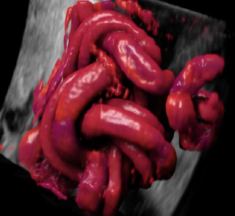

4、9大胎儿核心部位独立成像

E10独有的表面模式、血管模式、组织血管透明模式等智能诊断模式,对胎儿的体表、内脏、血管、骨骼等9大核心部位独立成像,全面弥补传统系统四维彩超在检测范畴及精准度的局限性。